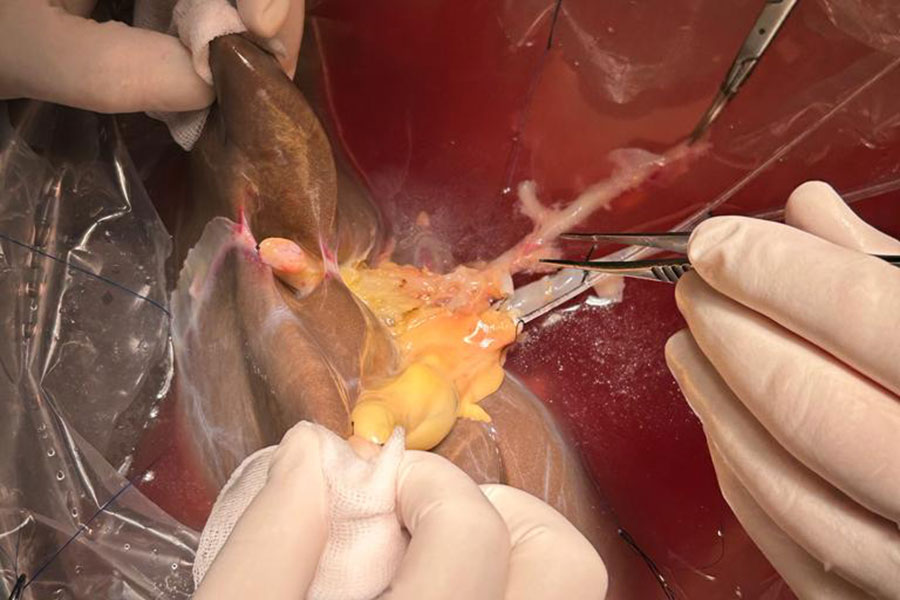

W Klinice Chirurgii Ogólnej, Transplantacyjnej i Wątroby UCK WUM wykonano pierwsze w Polsce przeszczepienie wątroby pobranej od dawcy zmarłego i podzielonej dla dwóch dorosłych biorców. To kolejny kamień milowy w programie transplantologii UCK WUM i kolejna szansa na zwiększenie liczby przeszczepień. Operacja przeprowadzona została przez zespół prof. Michała Grąta i polegała na przeszczepieniu prawej części wątroby dla jednego biorcy i lewej części wątroby dla drugiego biorcy. Rozpoczęcie programu przeszczepiania podzielonych wątrób było ogromnym wyzwaniem medycznym i organizacyjnym, możliwym do podjęcia dzięki doświadczeniu zespołu Katedry i Kliniki Chirurgii Ogólnej, Transplantacyjnej i Wątroby UCK WUM, którą kieruje prof. Grąt w zakresie operacji wątroby i dróg żółciowych. Stopień skomplikowania procedury odzwierciedla liczebność zaangażowanego zespołu: 15 chirurgów, dwóch anestezjologów, radiolog, pięć instrumentariuszek, cztery anestetyczki. Oba fragmenty wątroby podjęły funkcję po przeszczepieniu. Pacjenci są w dobrym stanie, bez powikłań pooperacyjnych.